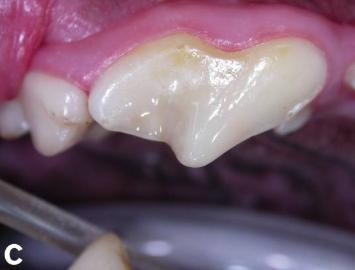

蛀牙情况修复中

而治疗方法通常是由小狗蛀牙损伤的阶段而决定,在前一、二阶段,也就是初期,兽医会将蛀牙部分的牙本质以其周围的牙釉质清除,并且杀菌后冠状物将通过汞合金填充物修复。

在第三阶段,也就是牙髓腔受损导致牙髓病,因为血液阻塞无法进入根管而导致牙齿坏死。这时候应该使用根管治疗,其包括去除坏死的牙髓组织,再进行消毒、擦洗根管,使用生物惰性材料填充根管,以及修复和密封受损的牙冠,在这阶段做这些处理能有效的防止牙龈疾病扩散到骨骼。

而到了第四、五阶段,则需要完全拔掉牙齿,并且在牙齿周围使用密封剂,以防止进一步的扩散。根据牙齿持续损坏的时间和面积,兽医会用精密仪器观察牙龈瓣内部,清除坏死组织并治疗,促进牙龈组织愈合。

蛀牙已得到完全修复